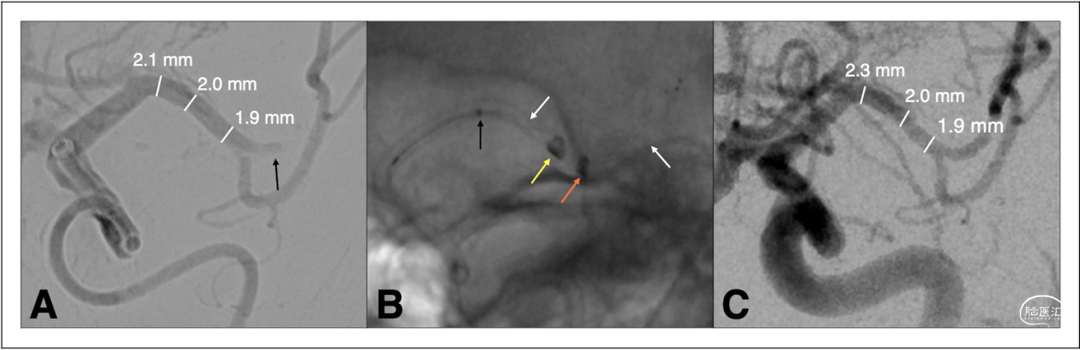

图1和图2显示了该研究中颇具挑战的血管解剖结构,包括多个>180°的成角和扭曲。该研究中使用的直径2.74mm的Zoom 88导管与直径较小的M1导管在尺寸上存在较大差异,但所有手术均未出现节段或明显的血管损伤(图3)。

图2.(A)一名NIHSS评分为20的六旬患者出现左侧M2(上支)远端闭塞(黑色箭头)。(B)使用Zoom 88(黄色箭头)和Zoom 71(橙色箭头)导航至M1,并通过Trak 21微导管(黑色箭头)在M2(上支)放置Trevo 4×28(白色箭头)支架取栓。(C)血管造影显示Zoom 88支架取栓后M1近端扩张达到TICI 3。